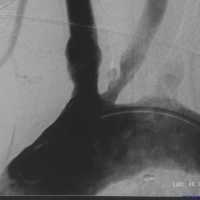

脑血管造影多普勒证实有颅内动脉狭窄者,药物治疗无效时,可考虑手术治疗。